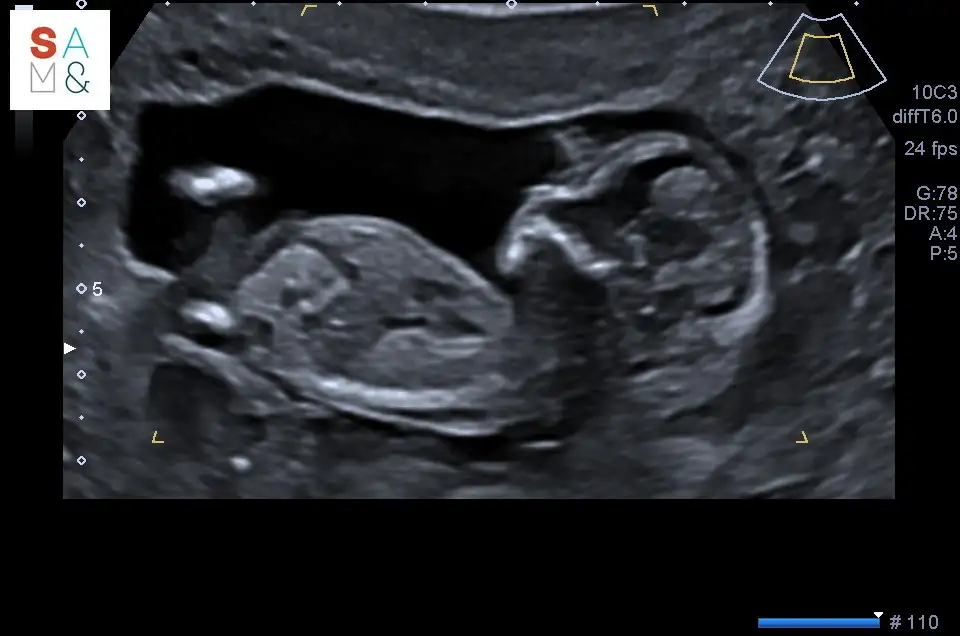

Herkese merhaba ,

Dün ciddi karın agrısı ile kıvrandım ve çok endişelendim bebek için.

Bugün detaylı ultrasonda iyi olduğunu öğrenince içim rahatladı . Hatta onu izlerken elimi alnıma koymuştum , kadın bak aynı senin gibi duruyor eli basında dedi . Keyif bebesi resmen ..

Cinsiyeti yine söylemedi :) 2 hafta daha bekliyoruz .